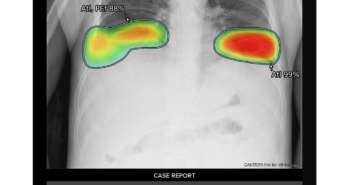

의료 인공지능(AI) 기업 루닛이 싱가포르 국영 의료기술 기관 시냅스(Synapxe)가 공공의료 서비스 혁신을 위해 새로 선보인 의료AI 플랫폼 ‘AimSG(AI Medical Imaging Platform for Singapore)’ 구축사업 입찰에서 최종 사업자로 선정됐다. 시냅스는 싱가포르 국공립 병원의 IT시스템을 통합 관리하는 정부 산하 기관으로, 싱가포르 국공립병원에서 의료 데이터 관리를 하기 위해서는 반드시 시냅스의 시스템을 활용해야 한다. 시냅스는 최근 국가 의료AI 플랫폼인 AimSG 서비스를 론칭하며, 흉부 엑스레이 AI 영상분석 솔루션에 대한 글로벌 입찰을 진행했다. 루닛은 해당 입찰에 참여해 최종 사업자로 선정됐으며, 이에 따라 흉부 엑스레이 AI 영상분석 솔루션 ‘루닛 인사이트 CXR’을 시냅스에 본격 공급하게 됐다. 시냅스는 AimSG 서비스를 싱가포르 국립종합병원(Singapore General Hospital), 창이 종합병원(Changi General Hospital) 등 싱가포르 주요 국공립병원에 설치할 계획이다. 설치 이후 루닛 AI 솔루션은 AimSG 플랫폼을 통해 각 병원에서 활용될 예정이다. 서범석 루닛 대표는 “이번 시냅스와의 협력은 싱가포르 공공의료 혁신에 크게 기여하는 등 루닛의 세계적인 경쟁력을 재차 강조하는 기회가 될 것”이라며 "특히 싱가포르는 아세안 지역의 중심 역할을 담당하고 있어 이곳에서의 성공은 아세안 전역으로의 확장을 위한 발판이 될 것으로 기대한다"고 말했다. 관련 기사 더보기 https://www.venturesquare.net/904645